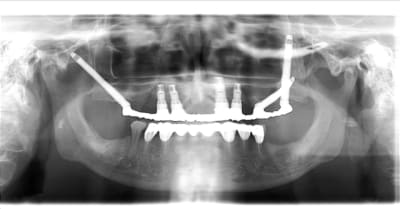

c'est du juxta osseux ca?

pas du juxta osseux ,ignare, des implants à plaque!

j'aimerais qu'on m'explique ce qu'on voit sur la pano précisément,

c'et spas ironique, c'ets juste pour savoir un truc.

Merci beaucoup.

> j'aimerais qu'on m'explique ce qu'on voit sur la pano précisément,

> c'et spas ironique, c'ets juste pour savoir un truc.

> Merci beaucoup.

L'oeil averti remarquera la présence d'un type d'implant particulier, les implants à plaque. Ces implants permettent d'équiper des patients qui ne pouvaient pas être traités jusqu'à ce jour. Ces implants ne sont pas encore recouverts d'os, les radiographies ayant été prises juste après la chirurgie implantaire. Mais nous savons qu'une fois équipé par ces implants, l'os va se régénérer et même croître sous la fonction.

Il est inutile de chercher ces implants dans un catalogue du commerce implantaire, ils sont, pour l'instant, uniquement disponibles pour les praticiens qui ont montré leur dextérité lors de leur formation en implantologie basale.